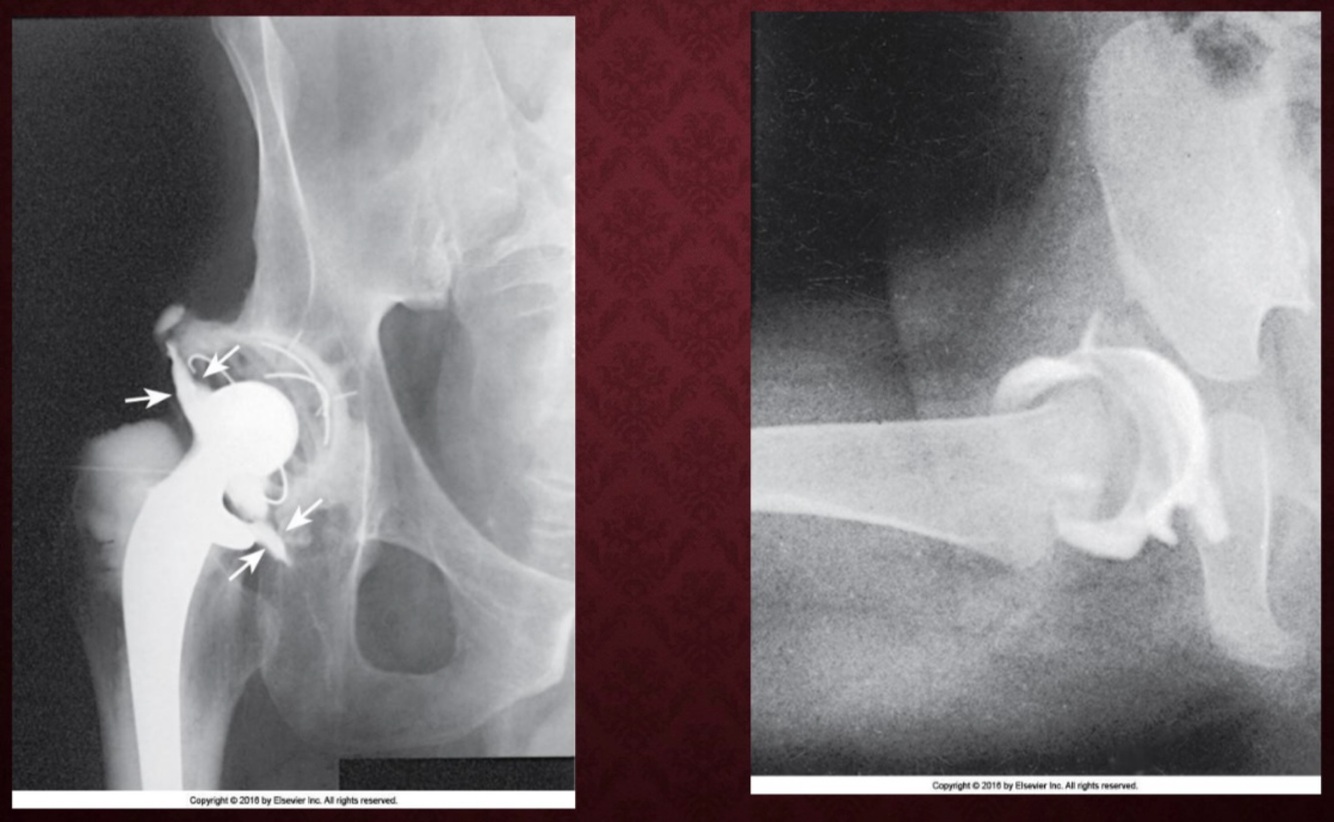

Hip Arthrogram

Joints commonly examined:

• Hip

• If contrast leaks into tissue surrounding the joint, it is evidence of a tear in the bursae or joint supporting ligaments